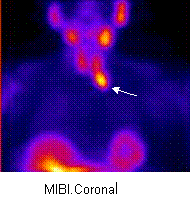

The Tc 99m-MIBI parathyroid SPECT scintigraphy shows a focus of increased MIBI

uptake at 10 min, below the left thyroid lobule and endothoracic, compatible

with a parathyroid adenoma (arrow). In the 99mTc pertecnetate image it is seen a

homogenuos uptake in the thyroid gland.